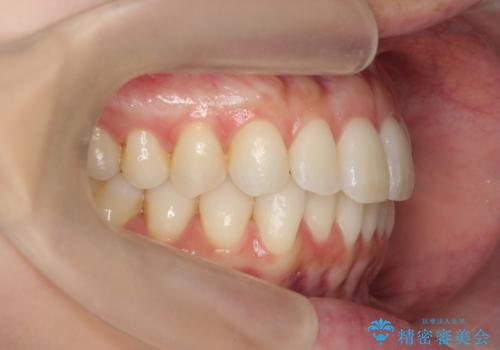

昔ワイヤー矯正をして後戻りした 軽度のがたつき モニター矯正

- 矯正治療後の後戻りを主訴に来院。

特に下の前歯のがたつきを気にされていました。

マウスピース矯正で再矯正を行いました。

再度の後戻りを防ぐため、下顎前歯の裏にはワイヤーを貼る保定を行っています。